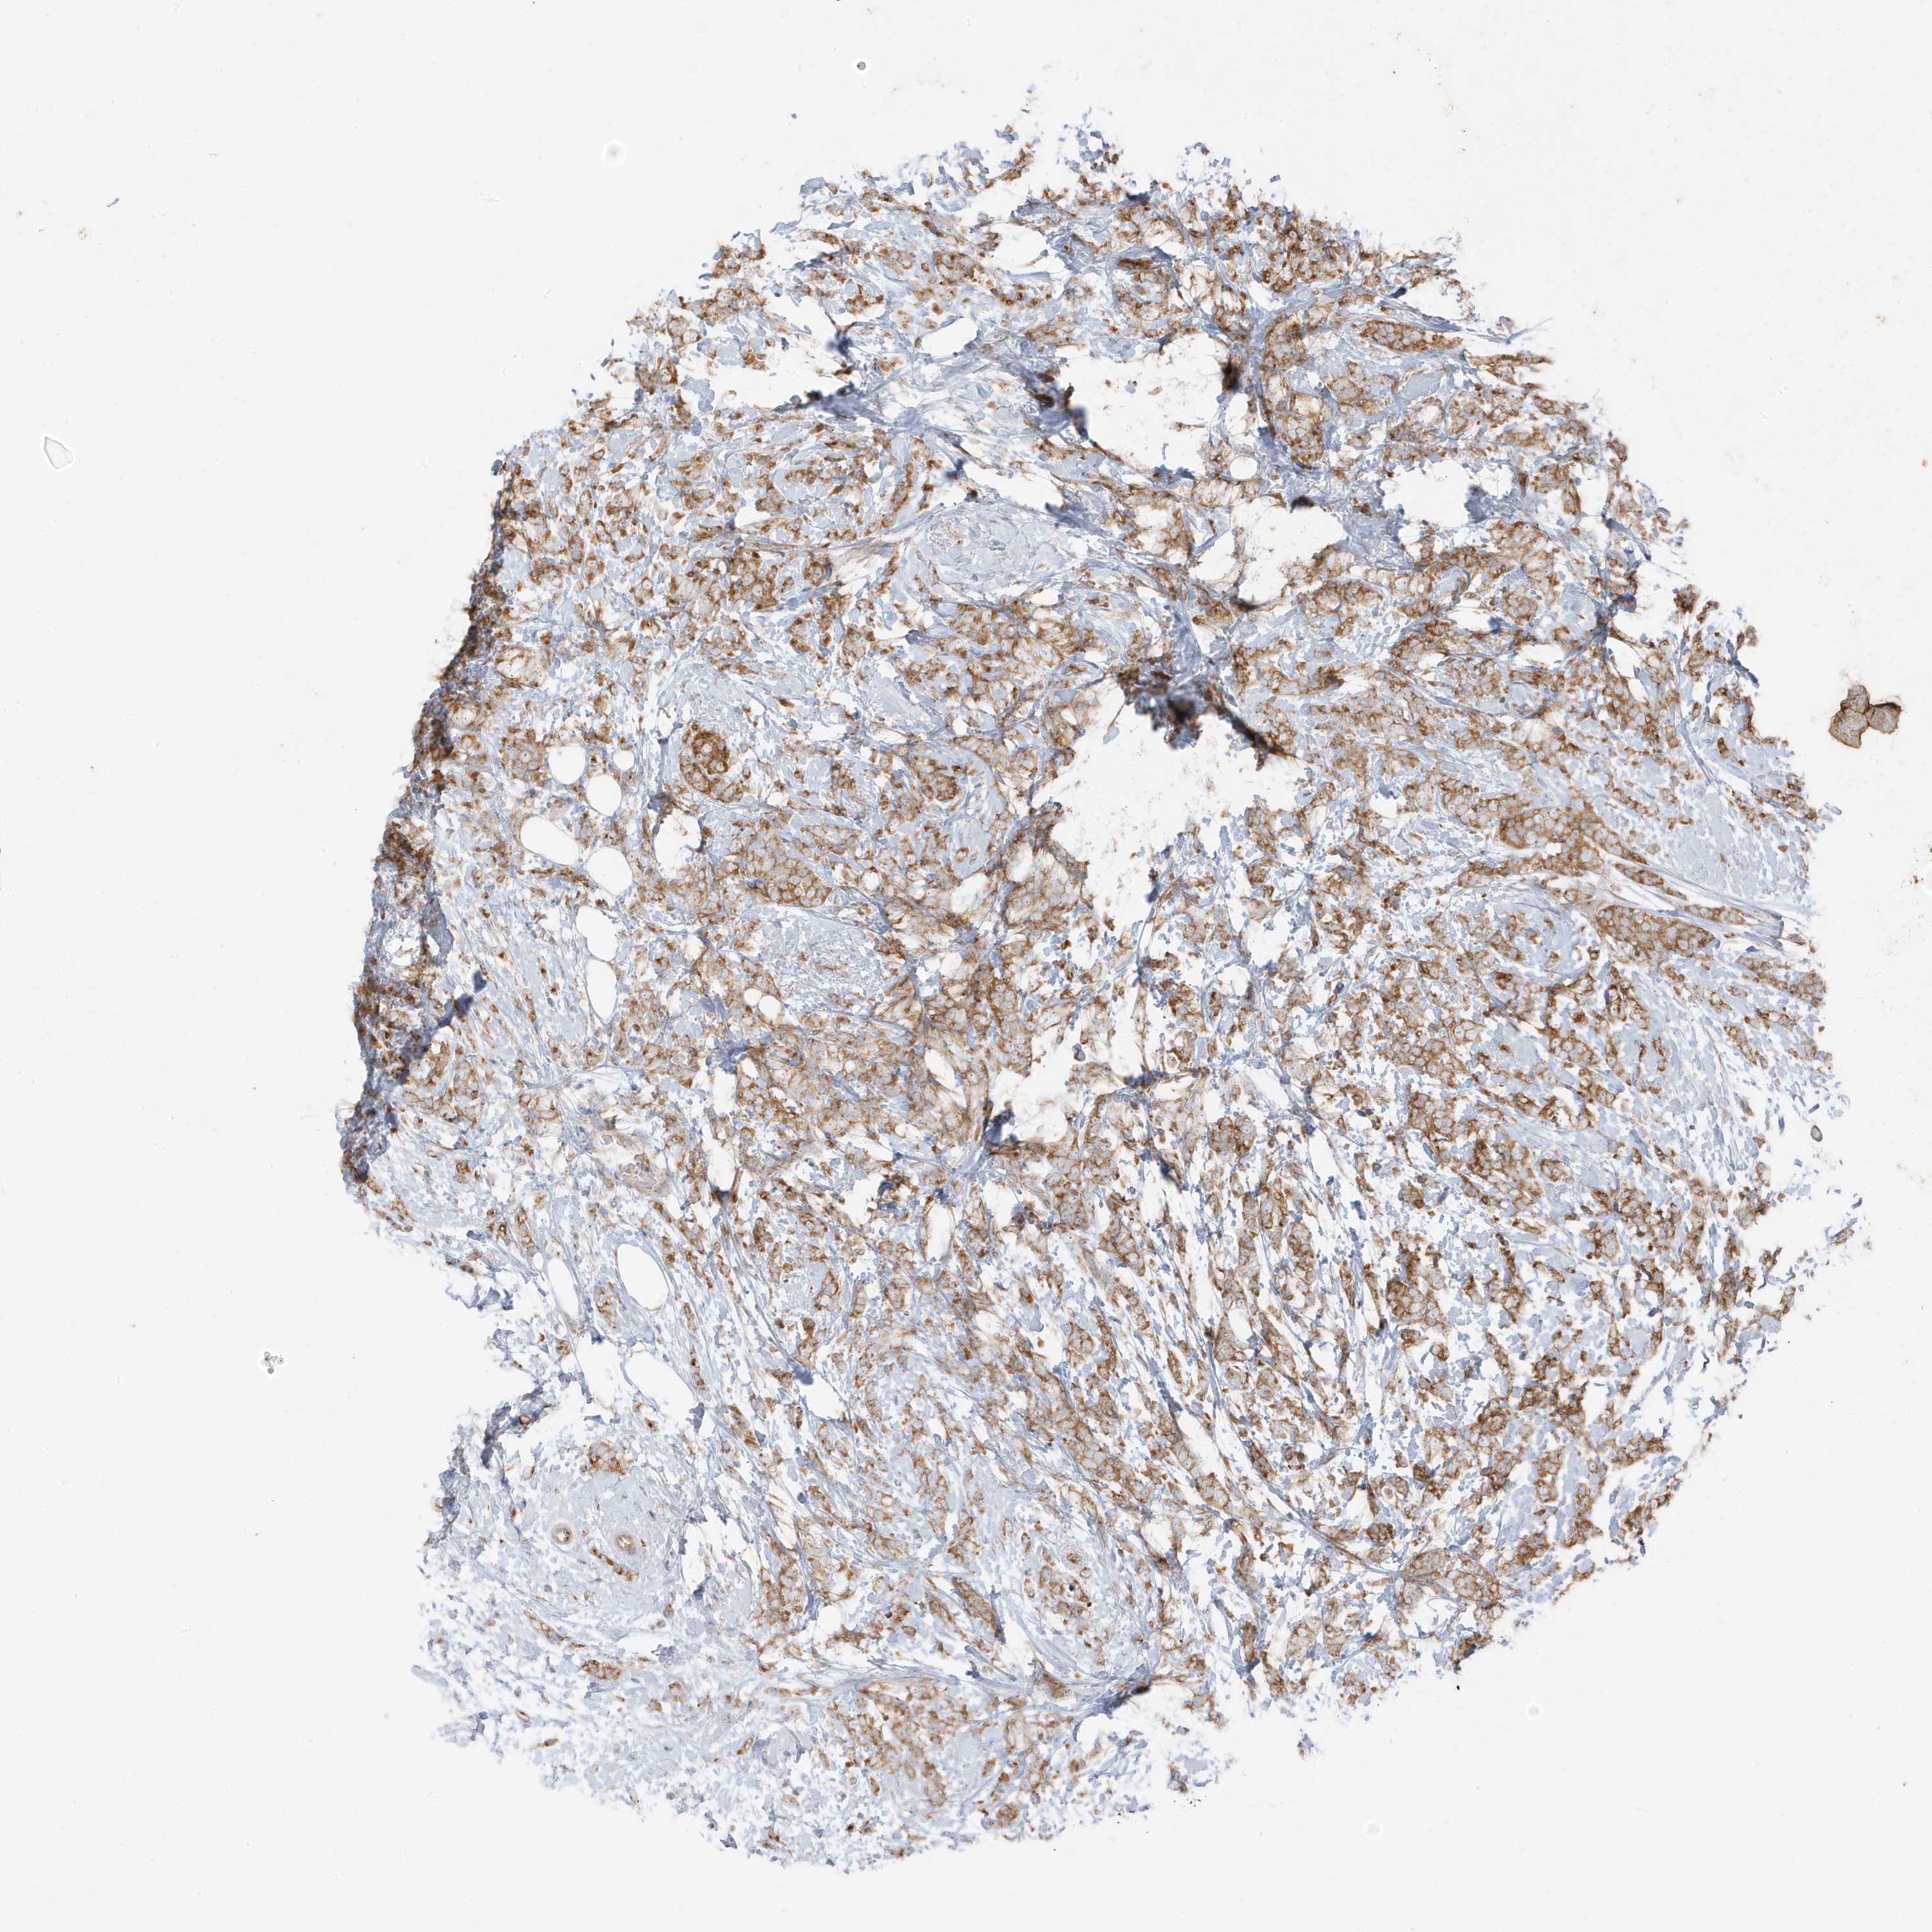

CANCER BREAST CANCER Show tissue menu

BRCA TCGA BRCA VALIDATION PROTEIN EXPRESSION